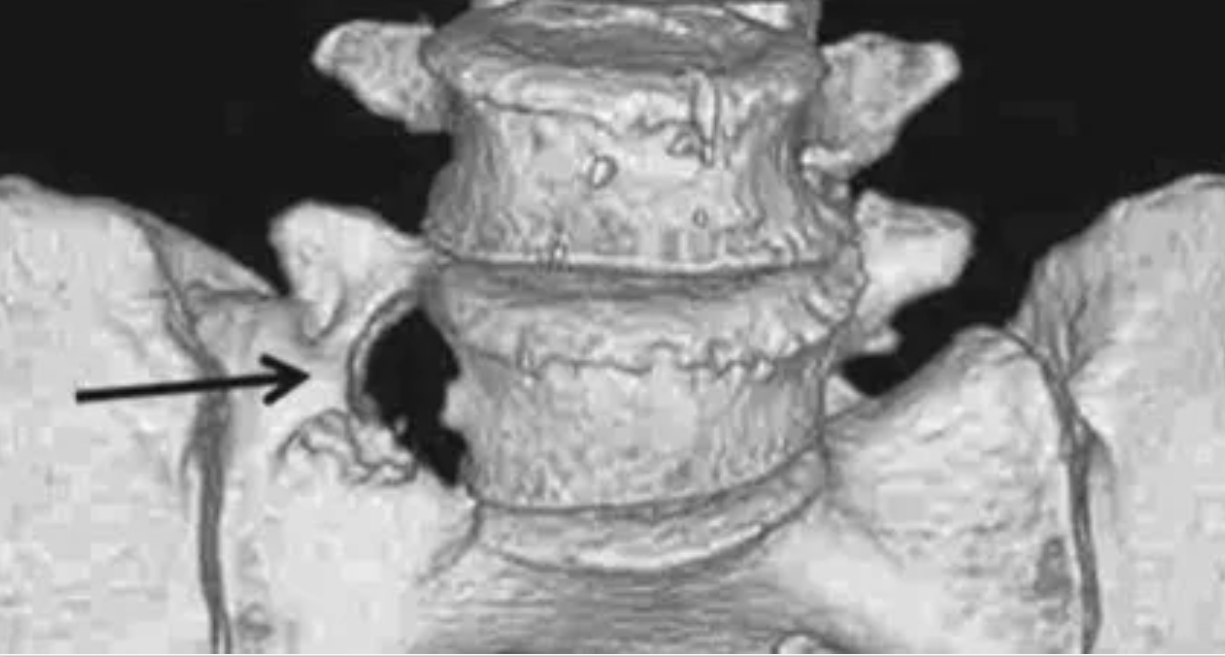

L5椎间盘呈远外侧型突出(黑箭)并与粗大的L5横突协同压迫L5神经根

IIIa型:三维CT显示右侧横突与骶骨嵴融合